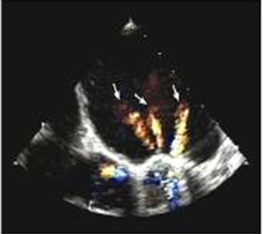

how many orifices do prosthetic bileaflet (st judes) valves have?

3 orifices (3 color jets)

where do we sample velocities?

there are 2 large orifices and one smaller.

sample flow from the smaller orifice with higher velocities